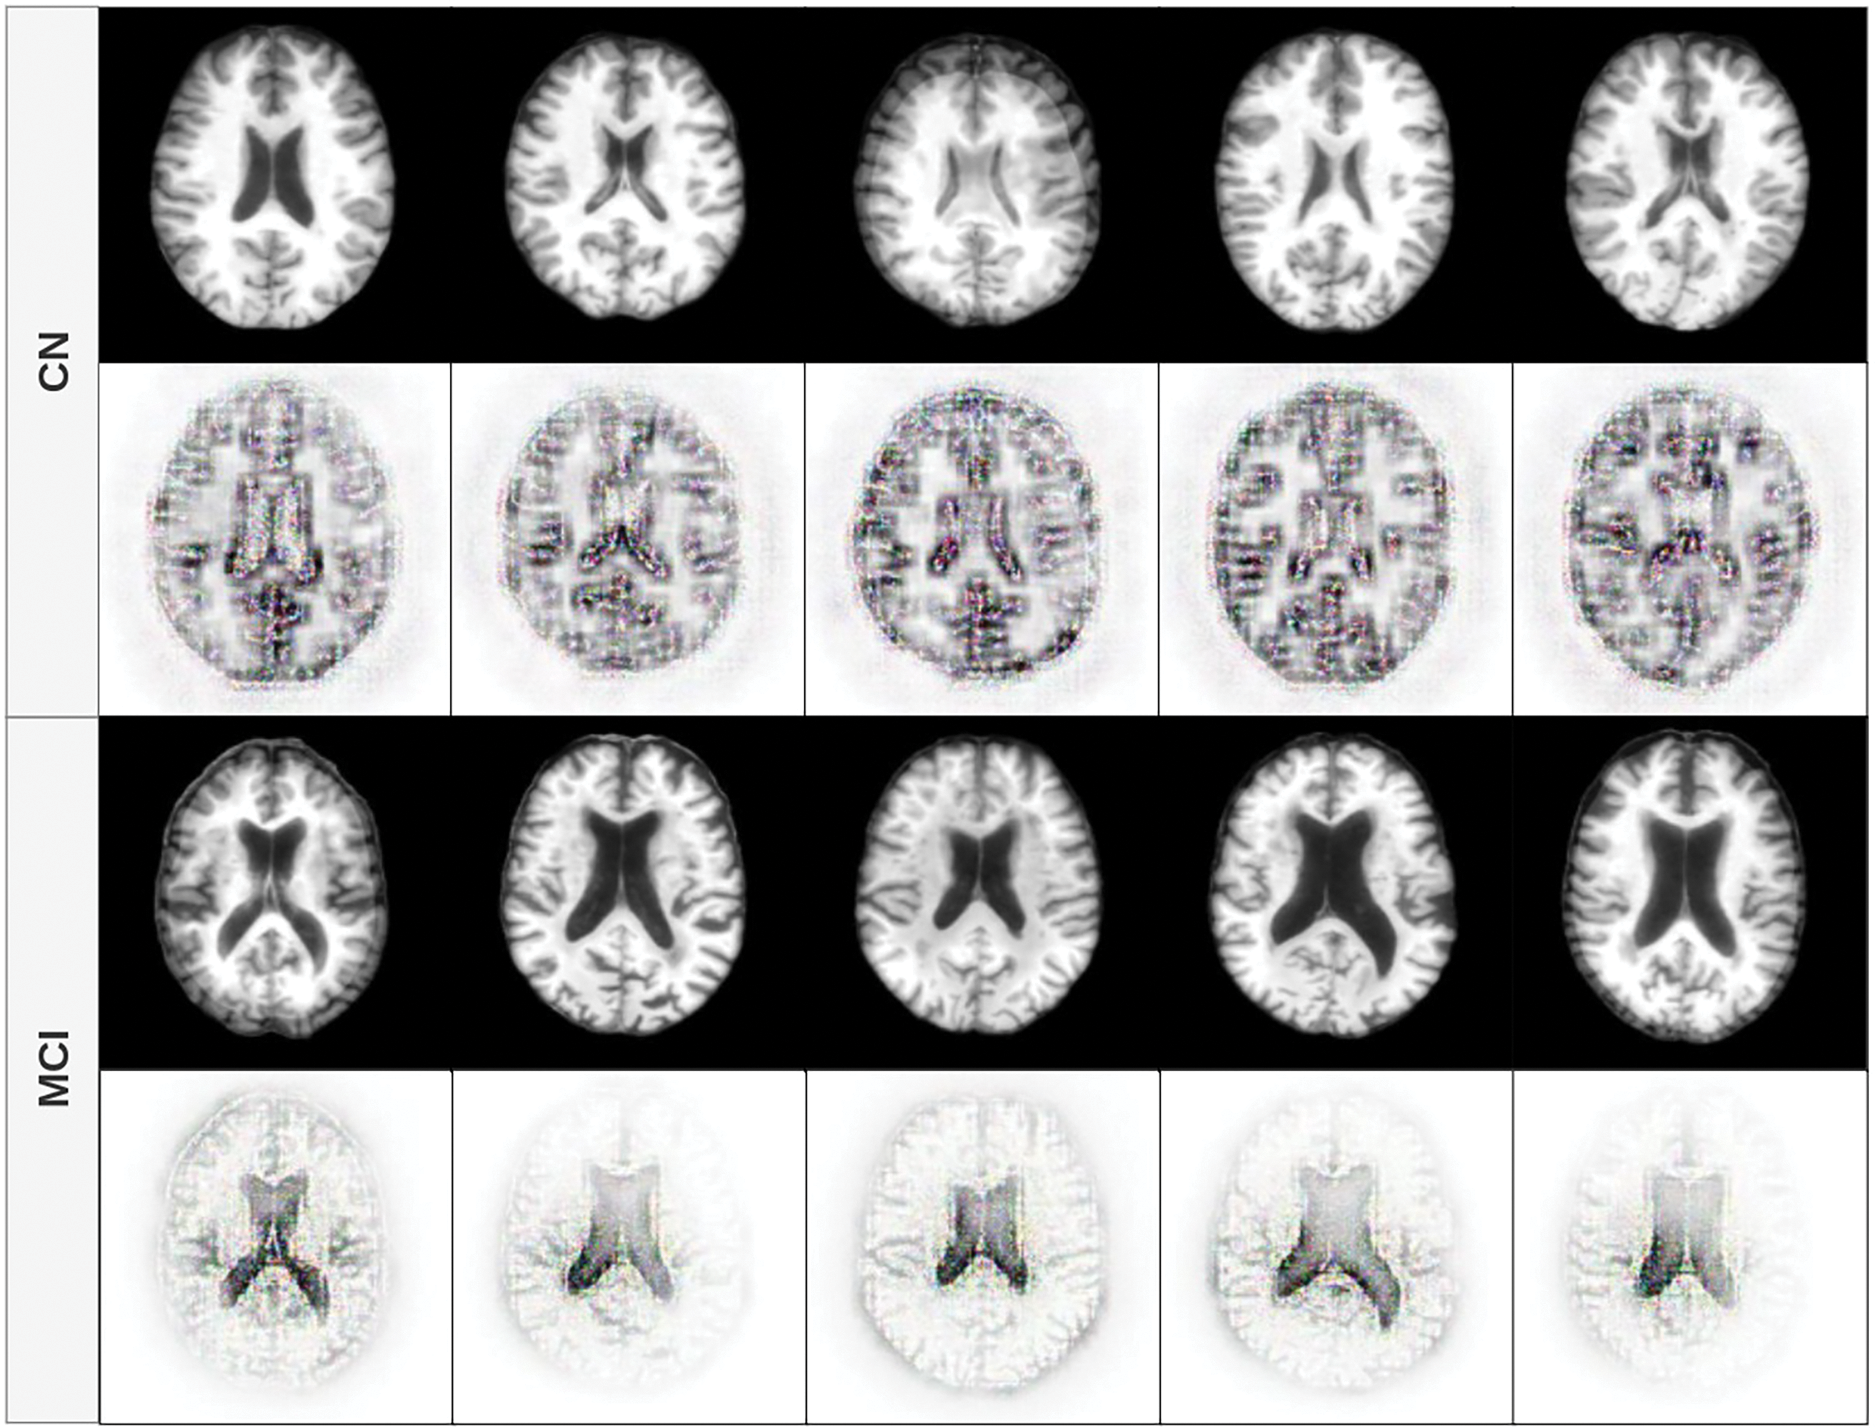

The figures in this subsection present selected visualizations of the most contributing features in different orthogonal planes–sagittal, coronal, and axial–using fused T1w and PiB-PET images. These visualizations help uncover spatial patterns that differentiate CN individuals from those with MCI and are aligned with known clinical markers of early cognitive decline.

Fig. 7 presents the axial view. In MCI subjects, consistent with the other planes, the highest contributions are observed in the central ventricular regions. In contrast, CN subjects show model attention primarily directed toward the outer edges and sulci of the brain. This again suggests that the structural integrity of the cortical surface and brain volume play a key role in the distinction of CN from MCI, reinforcing well-established neuroimaging findings.

Figure 7: Feature contribution visualization in the axial plane. MCI cases show attention in central regions, especially the lateral ventricles, while CN subjects have contributions from the cortical edges and sulcal patterns

4.5.4 Interpretation and Clinical Relevance

Across all planes, a consistent pattern emerges: in MCI cases, the model focuses on central brain regions, especially the lateral ventricles and midline structures, likely reflecting early neurodegenerative changes such as atrophy and ventricular enlargement. In contrast, CN cases draw attention to both central and peripheral areas, particularly the cortical boundaries, suggesting that the model is sensitive to preserved cortical morphology and brain volume, which are protective factors against cognitive decline.